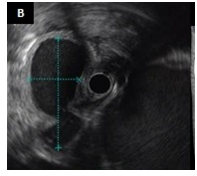

A 46-year-old male, with an alcohol-induced chronic pancreatitis, was admitted with epigastric pain. Laboratory data revealed an aspartate aminotransferase level of 98 IU/L (normal < 40), an alanine aminotransferase level of 85 U/L (normal <60) and a normal serum amylase level. Abdominal contrast enhanced computed tomography (CT) scan showed multiple pancreatic pseudocysts formations and a cystic lesion with 5,9 x 2,5 cm in diameter in the pancreatic head extending to the gastric wall which had an almost entirely intraparietal location Figure 1(A). Upper gastrointestinal endoscopy revealed bulging of the wall in the posterior portion of the gastric body, whose study by endoscopic ultrasonography confirmed the presence of a gastric intramural pseudocyst, with 55 mm in largest diameter, and with solid waste Figure 1(B). The pain resolved spontaneously, and therefore the patient was maintained on surveillance. Three months later abdominal CT showedspontaneous drainage of the intramural pseudocyst Figure 1(C).

Figure 1A Contrast enhanced abdominal-CT scan: multiple pancreatic pseudocyst formations and a cystic lesion with 5.9 x 2.5 cm in diameter in the pancreatic head extending to the gastric wall which had an almost entirely intraparietal location.